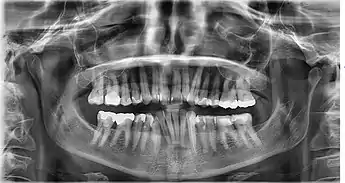

تصوير شعاعي سني

- أشعة بانورامية Panoramic: يظهر حالة الأسنان والأنسجة المحيطة بها لمنطقة الفكين (العلوي والسفلي) كاملة والمفصل الفكي الصدغي والجيوب الأنفية.